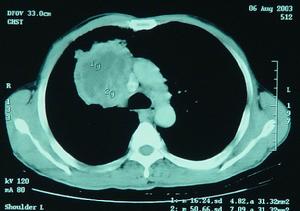

(2)、肺癌的CT 表現:胸部CT 對常規胸片上難以顯示的肺隱蔽部位,如胸骨後方、心後區、脊椎旁、奇靜脈食管窩、肺尖部肺門後方、後肋膈角等處腫瘤的顯示明顯優於X 線片。螺鏇CT(spiral CT)對病灶大於3mm 者多能發現。它對轉移癌的發現率比普通段層高。